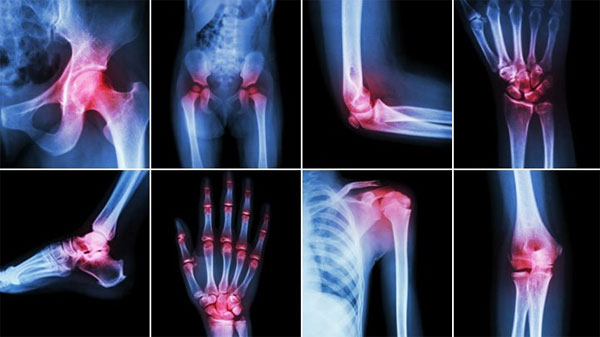

При повреждениях суставов необходимо получить наиболее подробные данные о целостности связок, формировании отечности и воспалительной реакции. Лучше всего для этих целей подойдет резонансное обследование. МРТ суставов проводится для оценки травм, полученных в результате повреждений в спорте или быту. Диагностика подобного плана проводится, когда у пациента нет никаких явных деформаций, но человек испытывает болезненные ощущения. Основная задача обследования — найти повреждения связок и провести оценку мягкотканых структур.

На МР-скрининге можно увидеть следующие деформации:

- новообразования в костных структурах и околосуставных тканях;

- артрит хронического типа;

- заболевания дегенеративного характера;

- инфекционные болезни воспалительного плана;

- грыжи, остеомиелит;

- ущемления и разрывы.

Томография предписывается врачом при травмировании из-за физического перенапряжения, вывихах, болезненных ощущениях без видимых причин или отечности, переломах, опухании.